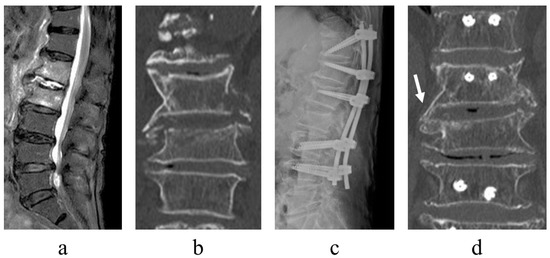

- Infection control. With minimally invasive posterior fixation and sensitive antibiotics, the inflammatory response normalized at an average of 42.8 days postoperatively. Previous reports stated that the period of normalization of the C-reactive protein concentration ranged from <1 month to 3 months; however, it was 42.8 days in this series [5,16]. In numerous patients, infection control was achieved without requiring additional surgery, thus implying that this technique is useful for infection control.

- Early ambulation. Less invasive procedures and pain reduction aid early ambulation. Herein, surgery significantly reduced pain (NRS for preoperative lower back pain was 5.9, which improved to 3.6 at the postoperative period of ambulation) and induced early ambulation (patients were able to ambulate at an average of 2.7 days postoperatively). For pain relief and time to ambulation, the results were comparable with those of previous studies [17,18]. Even in older patients, the minimally invasive procedure may enable early ambulation.

- Alignment maintenance. Local kyphosis, which is exacerbated by the destruction of the disk or vertebral body due to infection, is a measure of alignment maintenance. Minimally invasive posterior fixation improved local kyphosis by 6.6 degrees, with a postoperative correction loss of 3.6 degrees, which is comparable with results reported in previous studies (range: 3.4–6.8 degrees) [11,15,16]. These findings suggest that the range of fixation and fixation strength in this series were sufficient to maintain local alignment.